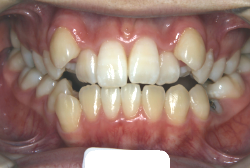

「歯並びの凸凹を直したい」という主訴で来院したケースです。診断の結果、たしかに「叢生」という隙間が足りないと言うことが原因の凸凹症例でした。

しかし、それ以上に問題なのは「前歯の噛み合い方が深すぎる」という症状で、初診の歯の正面写真を見ると下の前歯が全く見えません。こういう症状を矯正学では「過蓋咬合(かがいこうごう)」と言います。過蓋咬合を放置すると、将来的に顎関節に悪影響を与えるとされており、顎関節症の原因因子の一つです。また下の前歯の先端が、上の前歯の裏側の歯茎と強く接触するため、歯周病の原因にもなります。

検査の結果、凸凹が軽症なため非抜歯で矯正すること可能と判断、マルチブラケット装置にて治療しました。治療後は歯並びが綺麗になっただけでなく、噛み合わせ的にも正しい状態が確立しています。